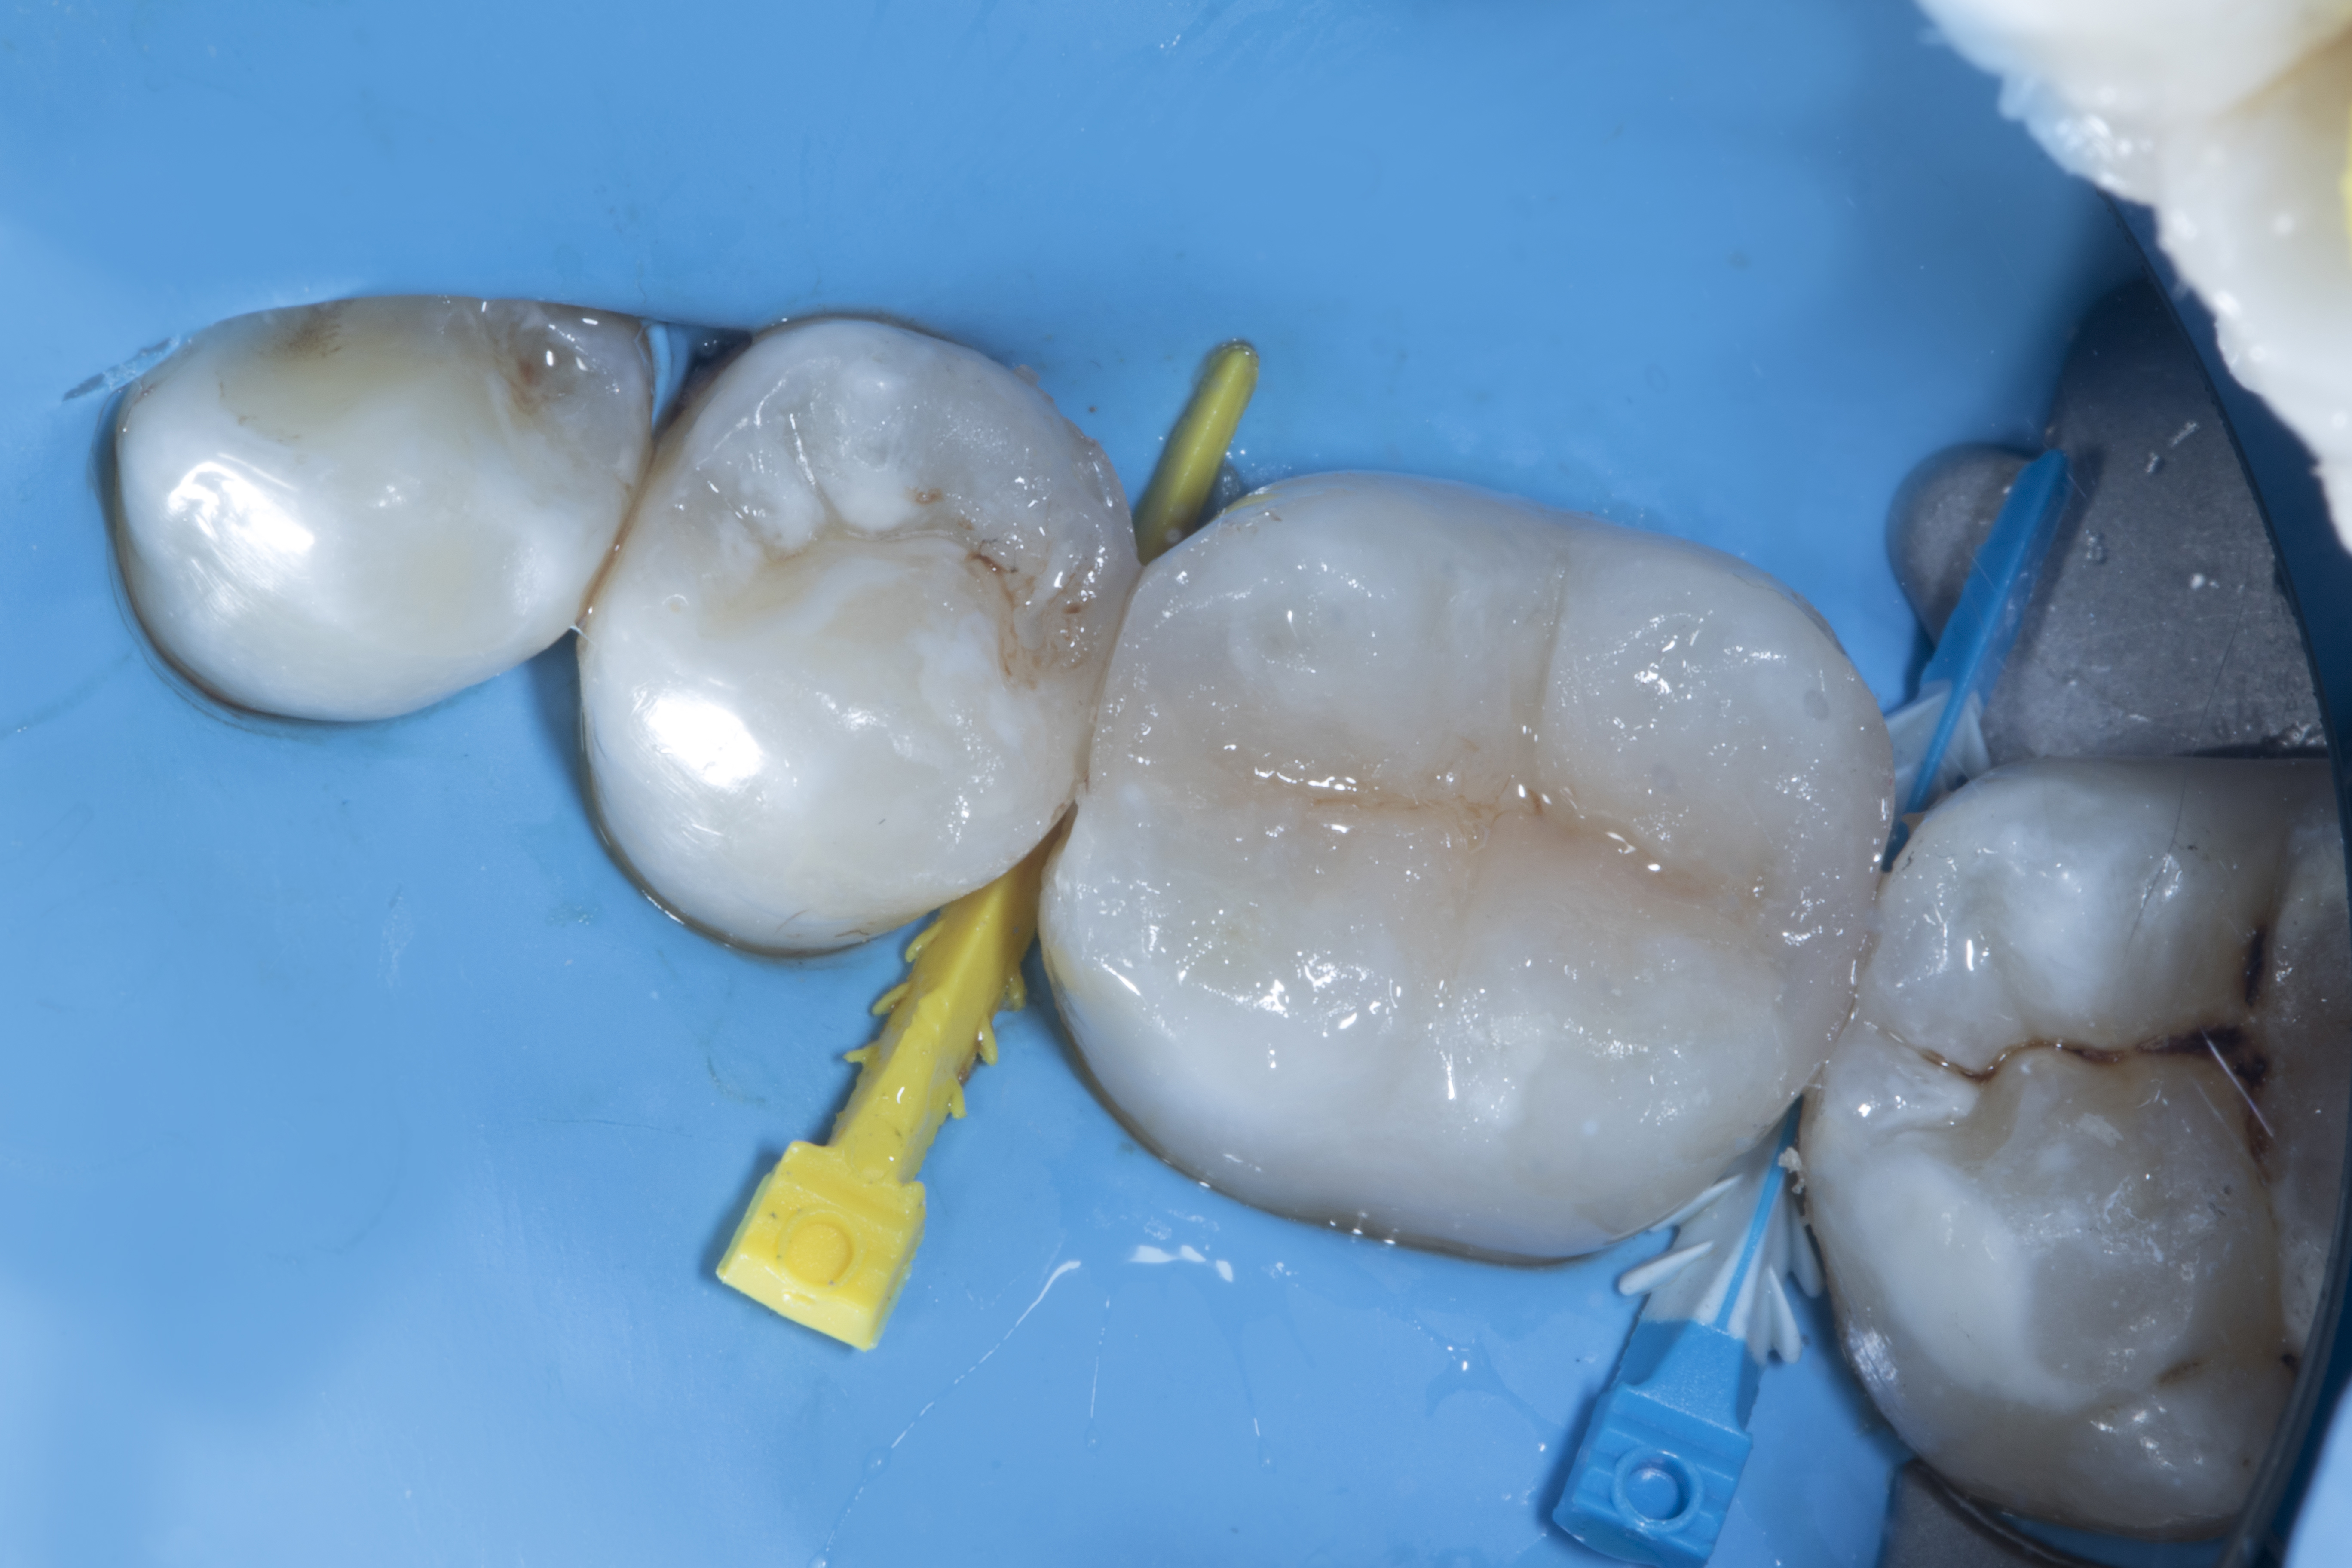

Step 3 – After removal of decay, the tooth was prepared using a small double-sided Super-Snap Purple disk to bevel the proximal box, remove sharp edges and unsupported enamel.

Clincial tip: This is the most important step if you want to achieve great margin seal and avoid microleakage.

Figure 3

Figure 3. After removal of decay, sharp edges and unsupported enamel and beveling of proximal box with the help of Super Snap (Shofu) double sided purple disk.